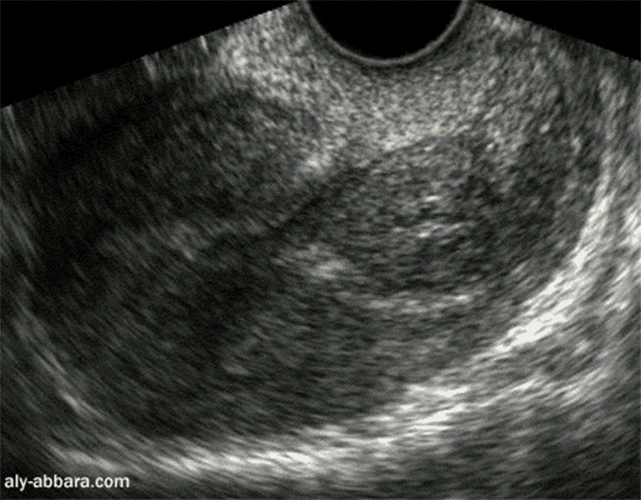

Rétention trophoblastique dans l'utérus

ou avortement incomplet

Il s'agit d'un avortement incomplet suite à une  I.V.G. médicamenteuse : la grossesse est détachée

complètement de la cavité du corps utérin et les débris trophoblastiques sont retenus dans l'isthme

et le canal cervical.

Rétention trophoblastique post-IVG médicamenteuse